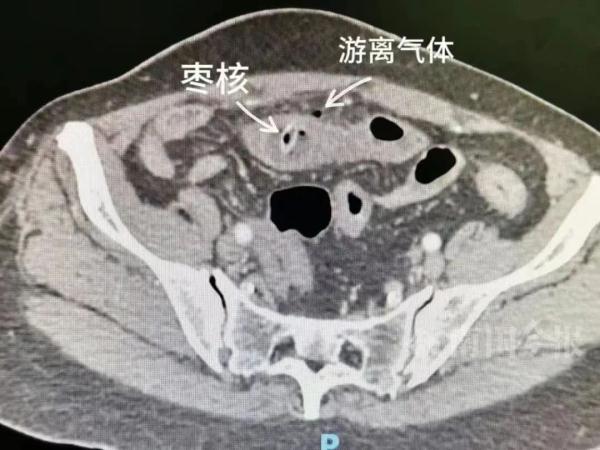

经过全腹部CT检查,医生在患者的小肠内发现了异物,并且观察到肠管水肿以及腹腔内存在游离气体。结合患者的叙述和CT检查结果,医生推断这很可能是由于小肠穿孔所导致的情况。

医生迅速为患者安排了手术,并在术中利用腹腔镜进行了异物探查和取出,随后缝合、修补穿孔部位。经住院做进一步观察与治疗,患者目前已康复出院。